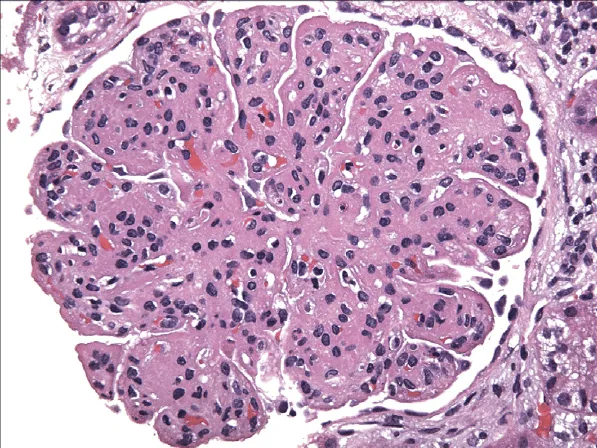

Como investigar a Membrano proliferativa de forma prática?

Como investigar a Membrano proliferativa de forma prática?Desvende a membranoproliferativa! Aprenda estratégias práticas e objetivas para investigar essa glomerulopatia desafiadora, otimizando diagnósticos e tratamentos na nefrologia.

Luís Sette

2 anos atrás